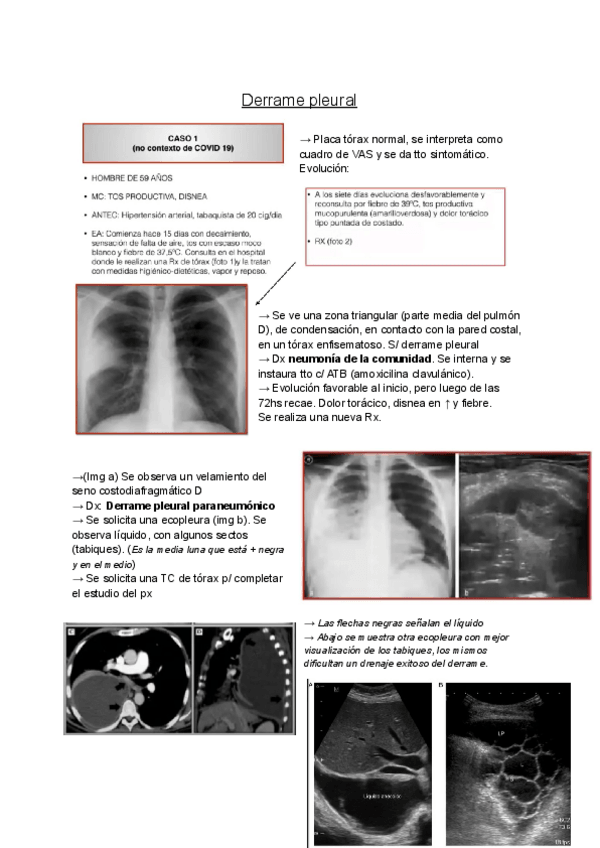

Apuntes - Derrame-pleural-.pdf